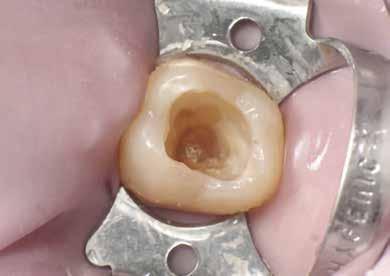

A cariest lépésről-lépésre távolította el, caries detektáló festék és a Peripheral-Seal koncepció [15] alkalmazásával, amely lehetővé teszi a magas kötőerejű, cariesmentes zománc- és dentinzóna kialakítását a kavitás peremén, miközben a mélyebben lévő, caries által érintett dentin megmarad remineralizáció céljából [16]. A preparáció szélét alumínium-oxid abrázióval kezelte a biofilm és az aprizmatikus zománc eltávolításának céljából, ezzel javítva a kötőerőt [17]; majd karbidfúrókkal elsimította, hogy eltávolítsa a mikroszkopikus szinten törött zománcprizmákat, így csökkentve a „Enamel Peel”-ből eredő fehér vonalak kialakulásának kockázatát (13. ábra) [18].

A fogat 37%-os foszforsavval kondícionálta, majd egy 4. generációs dentin bondot (Optibond FL, Kerr) alkalmazott. A II. osztályú dobozt először centripetálisan zárta [19], folyékony és melegített kompozit kombinációjával, szekciós matrica segítségével.

A dentint hiperkróm, közepes opacitású pasztakompozittal modellezte, amely optikai tulajdonságaiban utánozza a természetes dentint (14. ábra). A barázdarendszerbe okker árnyalatú színezőanyagot vitt fel a restauráció színintenzitásának fokozása érdekében (15. ábra).